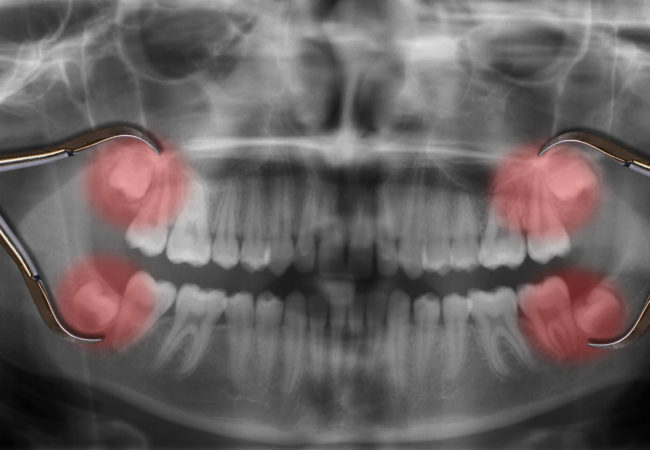

With an oral examination and x-rays of the mouth, Dr. Vanaria can evaluate the position of the wisdom teeth and predict if there are present or future potential problems. Studies have shown that early evaluation and treatment result in a superior outcome for the patient. Patients are generally first evaluated in the mid-teenage years by their dentist, orthodontist, or by an oral and maxillofacial surgeon.

If you do not have enough room in your mouth for your third molars to fully erupt, a number of problems can happen. Impacted wisdom teeth should be removed before their root structure is fully developed. In some patients it is as early as 12 or 13, and in others it may not be until the early twenties. Problems tend to occur with increasing frequency after the age of 30. Some of the possible problems related to not removing your wisdom teeth include: